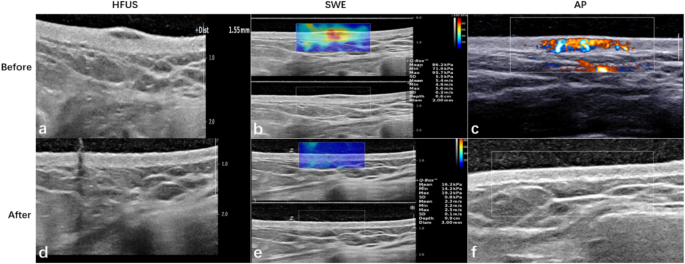

Multimodal ultrasound images of a good responder (case 1) before and after treatment. (a) HFUS shows a pre-treatment thickness of 1.55 mm, indicating keloid presence. (b) SWE indicates the keloid is hard, while (c) AP reveals high vascularity with abundant blood flow signals. Post-treatment, (d) HFUS indicates significant flattening, (e) SWE shows the keloid is soft, and (f) AP displays near-normal blood flow signals, reflecting reduced vascularity.

Multimodal ultrasound images of a poor responder (case 2) obtained from HFUS, SWE, and AP. (a) HFUS image before treatment shows a thickness of 3.26 mm. (b) SWE analysis indicates the keloid is hard, reflecting its stiffness. (c) AP image before treatment reveals sparse dot-like and linear blood flow signals, suggesting limited vascularity. After treatment, (d) HFUS shows thickness remains at 3.15 mm, indicating negligible change. (e) SWE analysis post-treatment indicates minimal alterations in keloid stiffness. (f) AP image after treatment demonstrates persistent sparse punctate blood flow signals.

After treating 28 keloids with the radioactive isotope 90Sr-90Y, we categorized them into two groups: good-responders and poor-responders. There were no reported adverse effects during the treatment sessions. We analyzed various ultrasound parameters before and after treatment for both groups to track their response to the treatment. Figure 4 shows representative clinical pictures of keloid with two sets of different treatment response before and after treatment, Fig. 4a depicts the state of the keloid in Case 1 before treatment, while Fig. 4b shows significant improvement post-treatment, indicating a positive response to the therapy. In contrast, Fig. 4c, d display the pre- and post-treatment condition of Case 2. Despite undergoing the same treatment, this patient exhibited minimal improvement, indicating a poorer response to the therapy. Specifically, in the good-responder group, elasticity parameters, including C-mean, C-max, C-min, E-mean, and E-max, exhibited a significant reduction (all P < 0.001), as did the E-ratio parameters. The P-values for C-mean-ratio, C-max-ratio, and C-min-ratio were all 0.003, while the P-values for E-mean and E-max were 0.006 and 0.013, respectively. The AP mode exhibited significant differences in vascular signal levels between the pre-treatment and post-treatment stages (P < 0.001), whereas both CDFI and PDI showed no significant differences (with P values of 0.134 for both). Although keloid thickness significantly decreased in both the good-responder and poor-responder groups after treatment (P < 0.001 and P = 0.041), there were no significant changes in elasticity parameters (P > 0.05) or color flow sonography modes (AP, PDI, and CDFI) when comparing pre-treatment and post-treatment stages (P = 0.170, P = 0.290, P = 0.827, respectively).